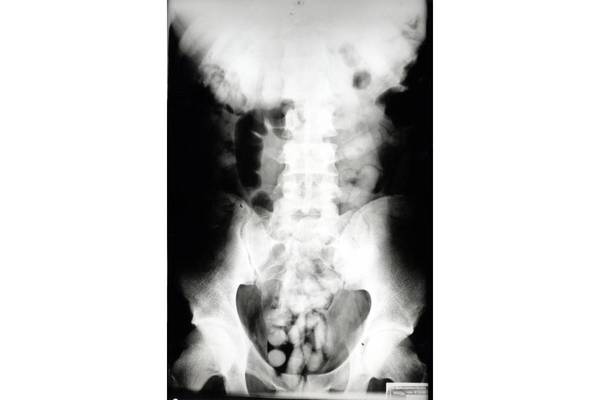

90 Schluckbehältnisse (sogenannte Bodypacks) haben Zöllner am Flughafen München am 26.06.2023 bei einem 36-jährigen Mann entdeckt, der aus Brasilien weiter nach Großbritannien reisen wollte.

Bei der Zollkontrolle verstrickte sich der Mann in Widersprüche, was seine Auskünfte über Reisezweck und -dauer anging. Die Beamten führten daraufhin einen Drogenwischtest durch, der das Kokain anzeigte. Da weder am Körper noch im Handgepäck des Kolumbianers Kokain gefunden wurde, musste der Mann im Krankenhaus geröntgt werden.

"Das Röntgenbild zeigte Fremdkörper auf und bestätigte damit den Verdacht der Zöllner", so Marie Müller, Pressesprecherin des Hauptzollamts München.